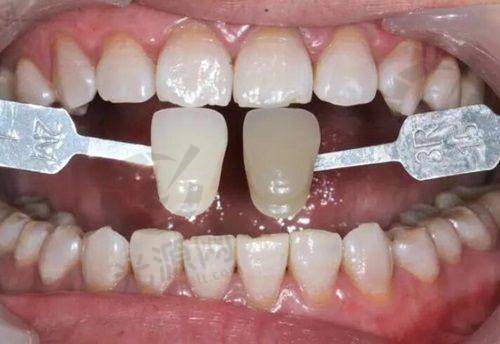

广州尚美口腔诊所是一家综合性口腔医院,集口腔种植、口腔矫正、口腔美容、口腔修复、儿童口腔、口腔综合治疗等多项目于一体。无论是牙齿缺失需要种植修复,还是牙齿不整齐想要矫正,亦或是进行口腔美容、修复等,在这里都能找到对应的诊疗服务。

比如口腔种植项目,能帮助那些牙齿缺失的患者重新拥有健康的牙齿;口腔矫正则可以改善牙齿排列不齐的问题,让患者拥有整齐美观的牙齿;口腔美容可以提升牙齿的美观度,让笑容更加自信;口腔修复能解决牙齿损坏等问题;儿童口腔专门针对儿童的口腔特点进行诊疗和保健;口腔综合治疗则涵盖了常见的口腔疾病治疗等。